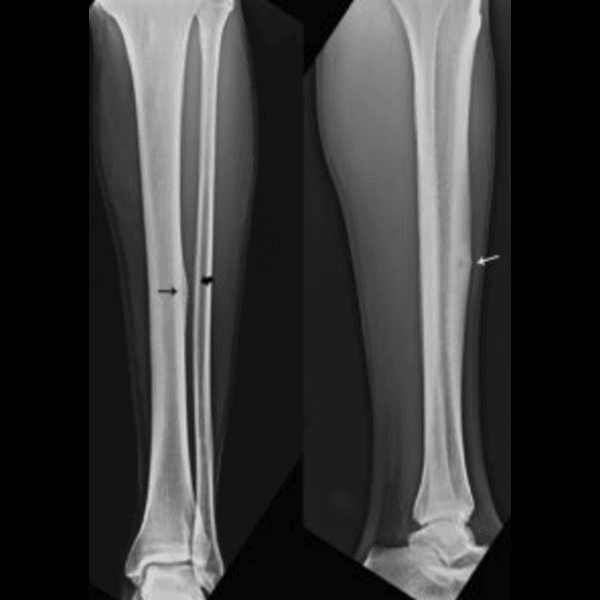

Stress fracture vs shin splints: what’s the difference? Shin pain is one of the most common issues runners experience. However, not all shin pain is the same. Two Read More